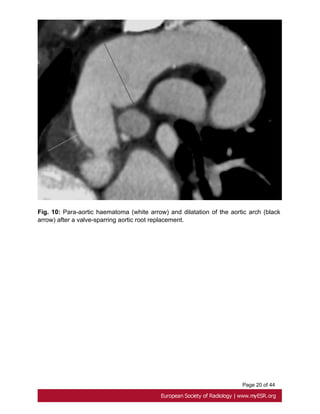

Fig. 8 on page 17, Fig. 9 on page 18, Fig. 10 on page 19

Fig. 10: Para-aortic haematoma (white arrow) and dilatation of the aortic arch (black

arrow) after a valve-sparring aortic root replacement.

Page 9 of44 or leak at proximal and distal graft anastomoses and at coronary reimplantation site [17]. Fig. 8 on page 17, Fig. 9 on page 18, Fig. 10 on page 19 • Aortic dissection Aortic dissection is characterized by separation of the layers of the aortic media initiated by a primary intimal tear[10]. Stanford type A dissection, which involves the ascending aorta, should be treated as a surgical emergency. Uncomplicated Stanford type B dissection, which is confined to the aortic arch and the descending aorta, can be treated with medical therapy[18]. Fig. 11 on page 20 ECG-gated CT is the first line investigation in acute dissection. Procedure include a non contrast study to look for intramural hematoma, and a contrast study. CT shows the false lumen which is separated from the true lumen by an 'intimal flap", and the extension of the dissection and any involvement of aortic branch vessels. Fig. 12 on page 21 MRI is recommended for long-term for follow up patients with Stanford B dissection, to appreciate changes in the size of the dissected aorta .Its use in the acute dissection is limited by a prolonged study duration [19]. Fig. 13 on page 23 • Bicuspid aortic valve Prevalence of bicuspid aortic valve in Marfan patients is about 5% whereas it is 1-2% in the general population. A bicuspid valve has two cusps instead of three; most commonly they are unequal size because of congenital fusion of one of the valves commissures [20]. Bicuspid aortic valve is generally detected by transthoracic echocardiography. ECG gated and contrast-enhanced CT shows two completely developed cusps and commissures [21]. Fig. 14 on page 23 • Mitral valve About 65 % of patients with Marfan's syndrome have mitral valve prolapse. Compared with myxomatous disease patients, Marfan patients have longer and thinner mitral valve leaflets, less posterior leaflet prolapsed and more anterior or bileaflet prolapse[22]. • Pulmonary artery

Page 20 of44 Fig. 10: Para-aortic haematoma (white arrow) and dilatation of the aortic arch (black arrow) after a valve-sparring aortic root replacement.